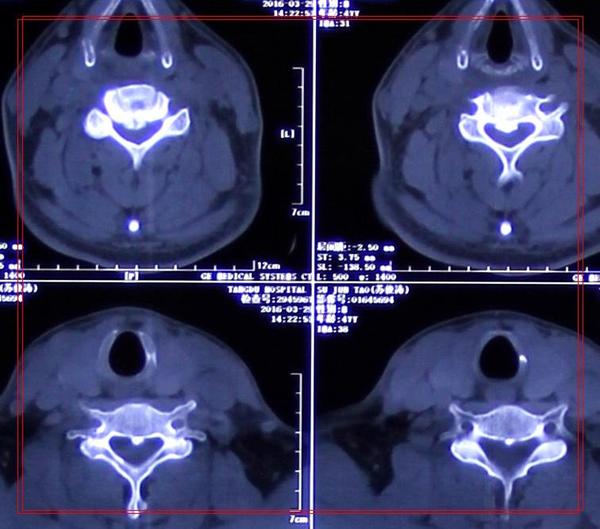

影像学资料